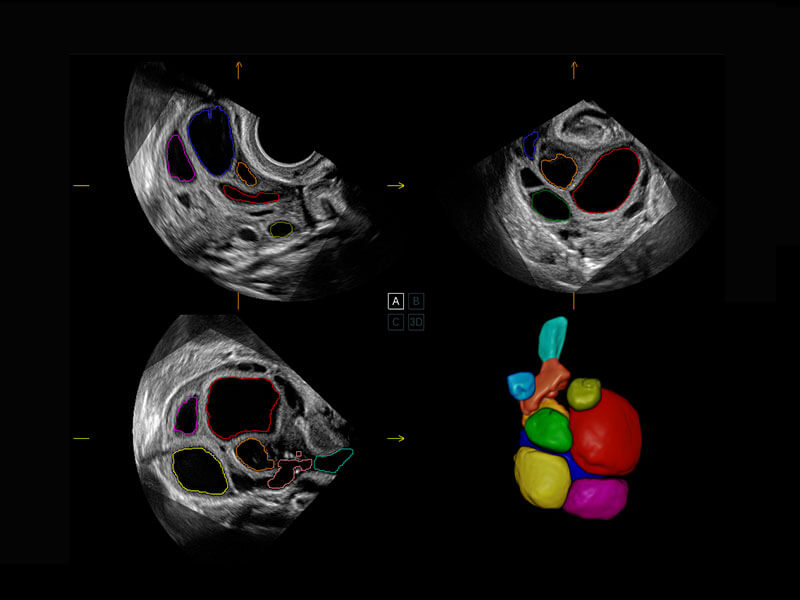

• 胎心容积成像

盆底超声

P60为盆底超声检查提供应用方案,多种腔内及腹部容积探头提供从二维、三维到四维的优异图像品质,实时快速三维容积数据获取,专业的测量工具包等人性化设计,为超声医生诊断提供有力保障。

Lev.Hiat A-r: 16.33 cm2

Lev.Hiat H-r: 53.70 mm

Lev.Hiat W-r: 43.96 mm

Lt-LUG-r: 24.16 mm

Rt-LUG-r: 19.94 mm

S-Pelvic

能够简化盆底检查的操作流程,可在二维模式及三维成像模式下实现一键自动提取出标准切面、自动识别当前切面、自动测量,提升盆底检查的高效性,同时也能让青年医生快捷的获得准确的检查结果。